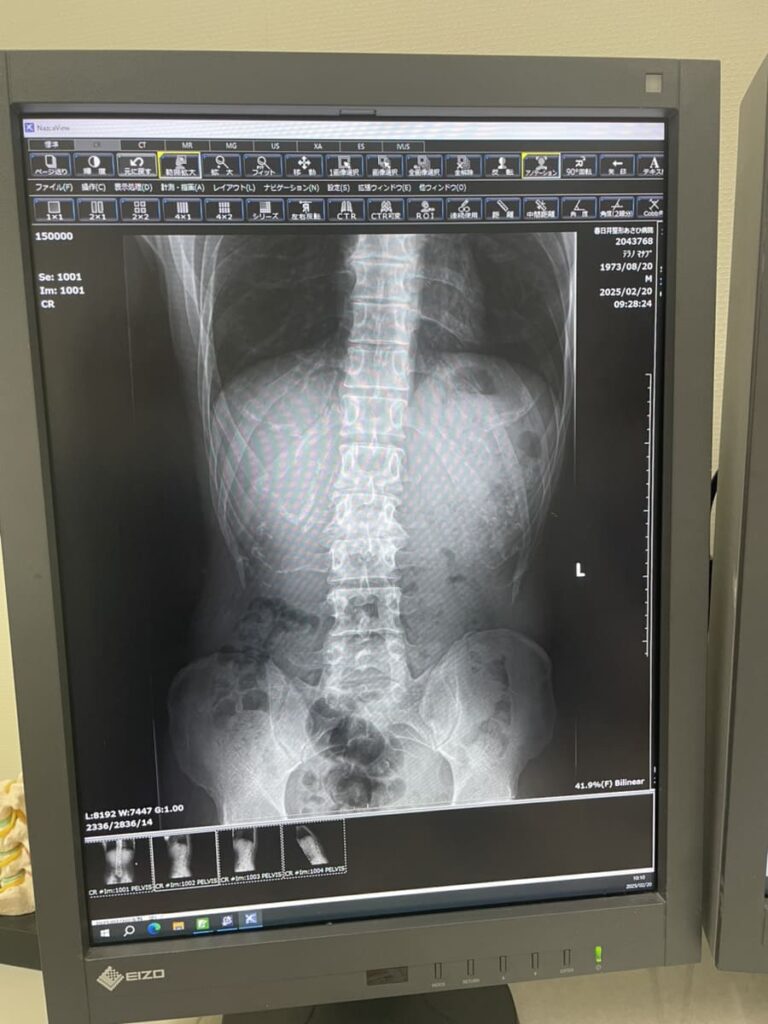

背骨が曲がっています。

↓画像を見てください,

レントゲン写真では、変形のある腰椎以外にも椎間が狭くなっている所がありますし、S字カーブが崩れているように見受けられます。

背骨が曲がっているのは今回のレントゲンで見ることが出来ましたが、曲がっているのは自覚していました。